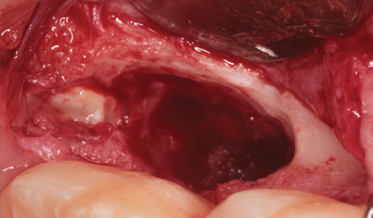

- Improving the Prognosis of Periodontally Involved Teeth at the Time of Extraction of Adjacent Teeth With an Amnion-Chorion Barrier and Bioactive Dentin Graft